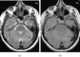

Normal-pressure hydrocephalus (NPH), also called malresorptive hydrocephalus, is form of communicating hydrocephalus in which excess cerebrospinal fluid (CSF) occurs in the ventricles, and with normal or slightly elevated cerebrospinal fluid pressure. As the fluid builds up, it causes the ventricles to enlarge and the pressure inside the head to increase, compressing surrounding brain tissue and leading to neurological complications. [Source: Wikipedia ]